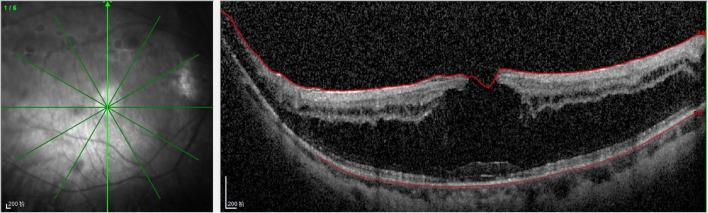

A 72-year-old Chinese woman with homocystinuria presented with a painless bilateral blurring of vision. The slit lamp showed the absence of lenses in both eyes. B-ultrasound and orbital computed tomography (CT) demonstrated bilateral posterior dislocation of the crystalline lenses, and spectral-domain optical coherence tomography (SD-OCT) revealed a lamellar macular hole and retinoschisis in the right eye. Biochemical examination demonstrated that the total homocysteine level was moderately elevated.

This report is the first to present an extensive and valuable description of bilateral intraocular lens dislocation with unilateral lamellar macular hole and retinoschisis secondary to homocystinuria. We have demonstrated that this case was spontaneous and chronic. CT is an effective diagnostic tool for patients with ectopia lentis. Early diagnosis and suitable management of patients with homocystinuria are essential to prevent these complications.